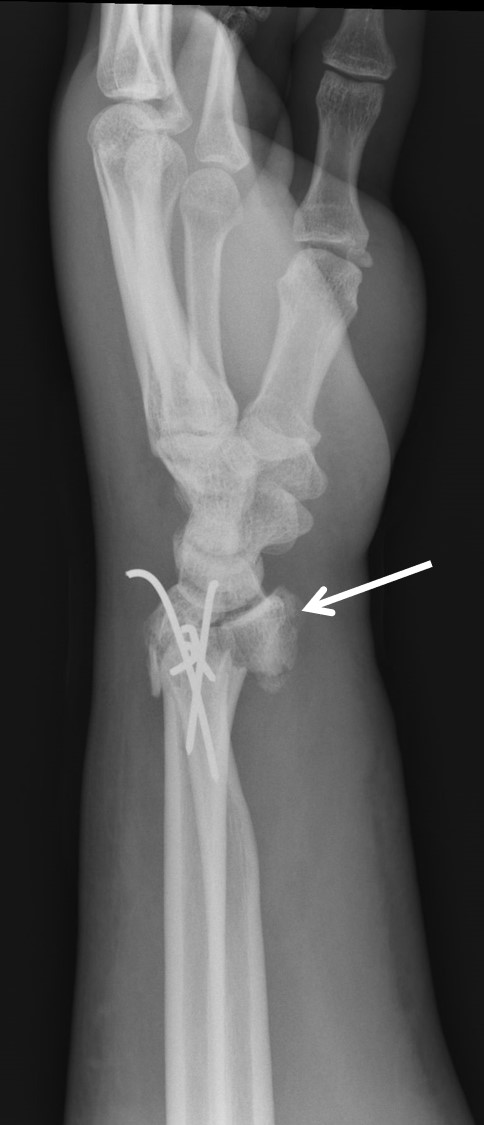

Treatment of neglected, displaced or united distal radial fractures (DRFs) is difficult, because it requires either wedging the almost consolidated fracture and reduction to the correct position, or cutting the united bone and putting it in the correct position (corrective osteotomy). Both treatments are associated with the risk of failure and complications. The paper presents a case of almost fully united DRF in a man, in whom 5 weeks after the injury, and after unsuccessful primary fixation with K-wires, the bone fragments were surgically wedged, aligned and fixed with a palmar plate. The result of treatment after 2 months was satisfactory. Early surgery allowed for a significant shortening of the recovery period and allowed the patient to return to work.